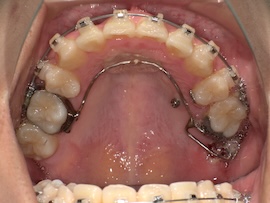

内側の装置が新しくなるので今回は型取りをして準備を進めていきます。

右上の6番目にバンド(金属の輪っか)を装着するためブラケットは一時的に外しています。

左上の奥に打っていた矯正用アンカースクリューですが、今回も安定せず揺れてきてしまったので抜くことになりました。

ある程度噛み合わせは良くなってきたのであとはゴムかけだけでも問題ないとのことです。

そして1ヶ月後、

牽引のため内側の装置が新しくなりましたが、これがびっくりするくらい話しづらいです…。